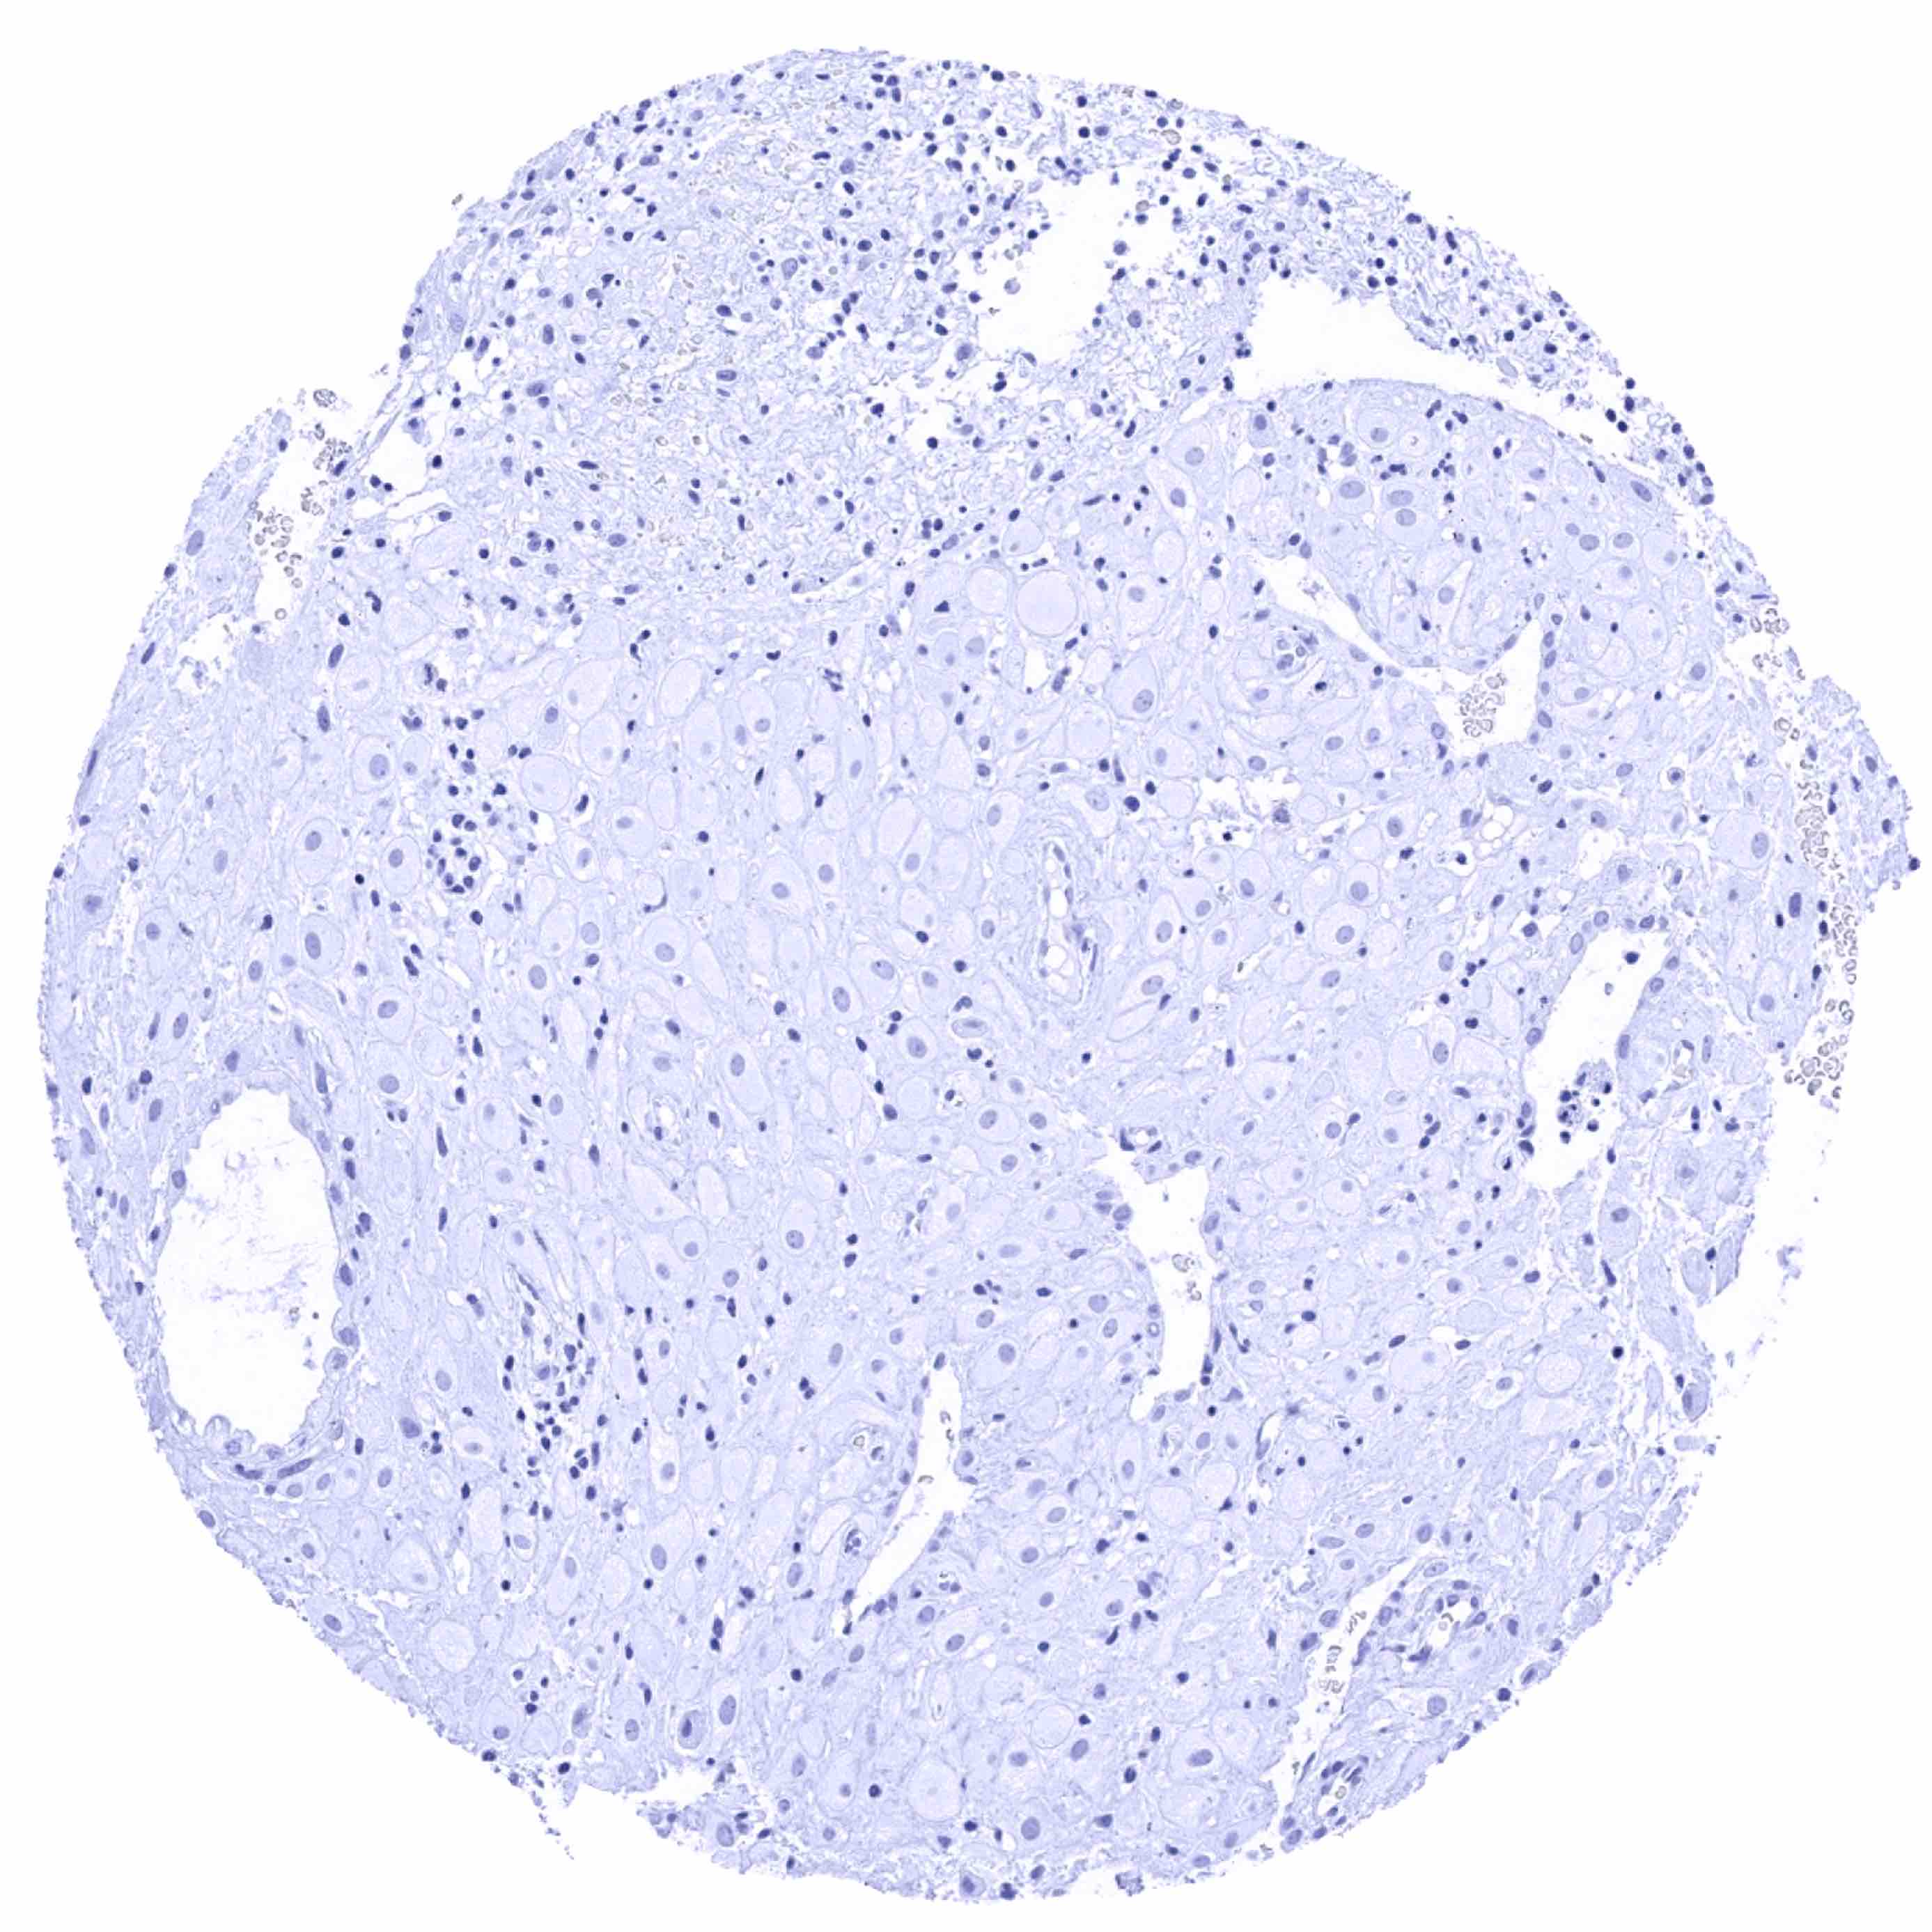

Kidney, cortex – Cytoplasmic (and nuclear) calbindin 1 staining of variable intensity in a fraction of distal tubuli

Kidney, cortex – Strong cytoplasmic (and nuclear) Calbindin 1 staining of a fraction of distal tubuli